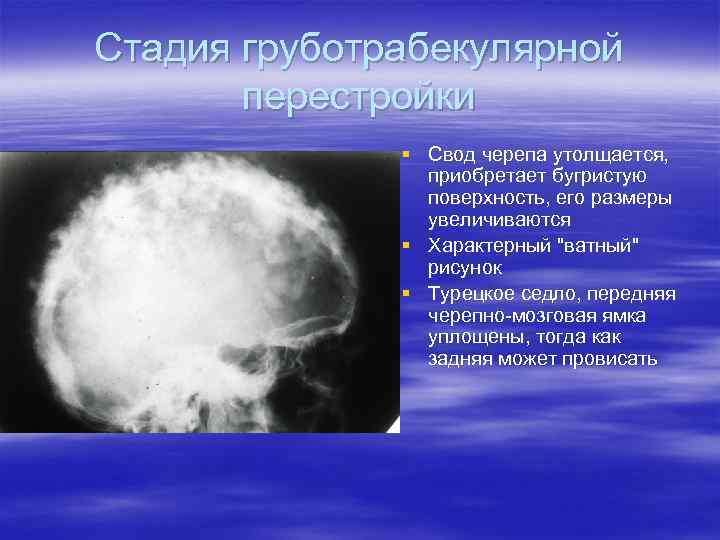

Рентгеновские снимки и визуализация болезни Педжета

Раздел: Мудрость в объективе